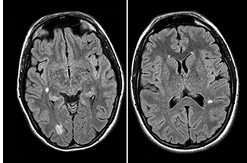

Un approccio clinico all’ipotono neonatale attraverso i casi

Castaldo B, Cossovel F, Starc M, Bua J, Travan L.

Una guida semplice sui segni clinici dell’ipotono, sulle ipotesi di diagnosi e sugli esami essenziali da non dimenticare. Può essere la manifestazione di varie condizioni, alcune gravi.